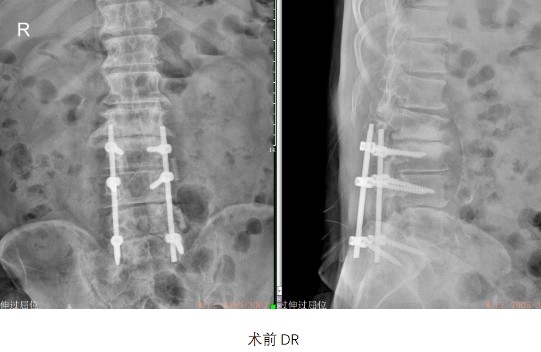

了解到病情和患者意愿后,孫主任邀請上海華山醫院脊柱外科張志玉教授搭乘當時往來滬甬兩地的輪渡跨越杭州灣,與孫建軍團隊共同完成了當年寧波為數不多的腰椎后路椎板切除減壓、椎弓根釘內固定術。

“當年手術理念先進,技術難度高,患者信任更是珍貴?!比缃褚淹诵莘灯傅膶O建軍主任回憶道,童老爺子是第一批“吃螃蟹”的人。

手術成功后,童老爺子不僅告別疼痛,更安然生活了近20年。這份療效,成為醫患互信的最佳注腳。